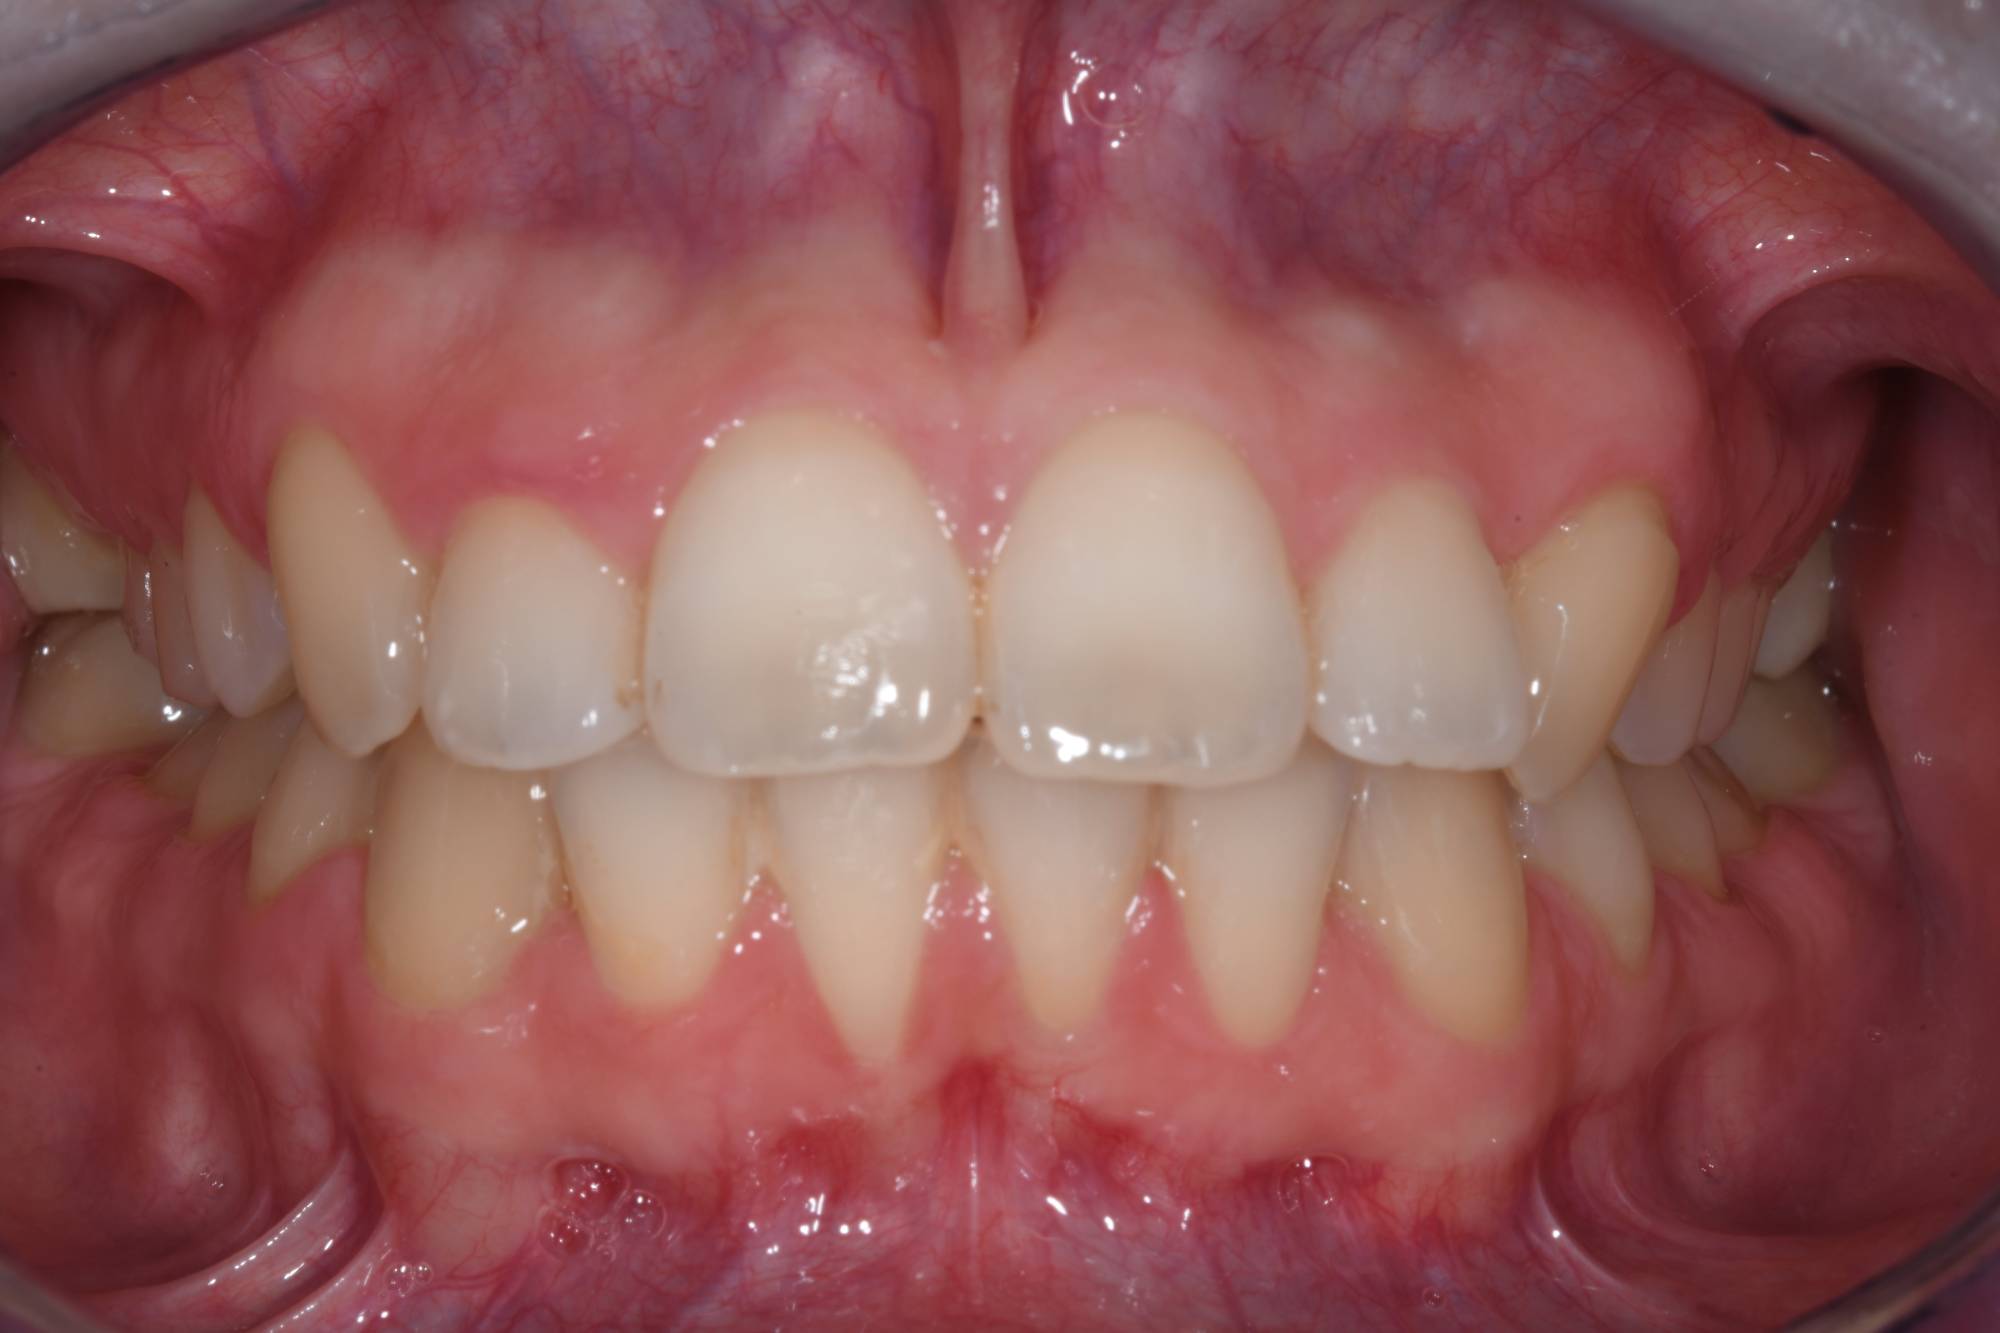

Ho applicato i brackets (gli attacchi metallici) sui denti. Dopo 12 mesi di terapia ortodontica abbiamo ottenuto il risultato che puoi vedere nell’altra foto. La masticazione adesso è corretta e i denti anteriori, superiori e inferiori, sono allineati. Ora può sfoggiare un sorriso smagliante e recuperare rispetto a tutte le foto che non ha osato scattarsi: un vero ritorno al futuro! La soddisfazione della paziente è enorme: masticazione più funzionale, migliore estetica e maggiore fiducia in sé stessa, finalmente adesso affronta la vita con più grinta.